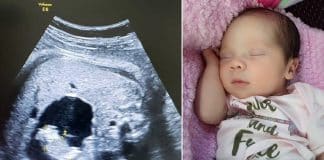

Uma bebê nasceu “grávida” na Colômbia. Entenda o caso!

Uma bebê nascida em Baranquilla, na Colômbia, veio ao mundo com uma condição muito rara conhecida como “feto no feto”. Estima-se que essa condição ocorra em cerca de um em cada 500 mil nascimentos.